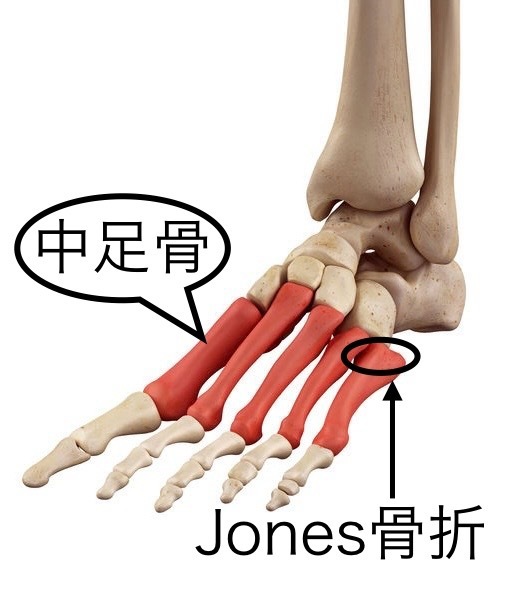

中足骨骨折(疲労骨折)

足関節を内向きに捻ることで起きる骨折や、ランニングやジャンプ動作による過度な体重負荷が長時間繰り返し中足骨に加わることで起こる疲労骨折があります。

第5中足骨近位部骨折が代表的で

①基部剥離骨折②Jones骨折③近位骨幹部骨折に分類される。